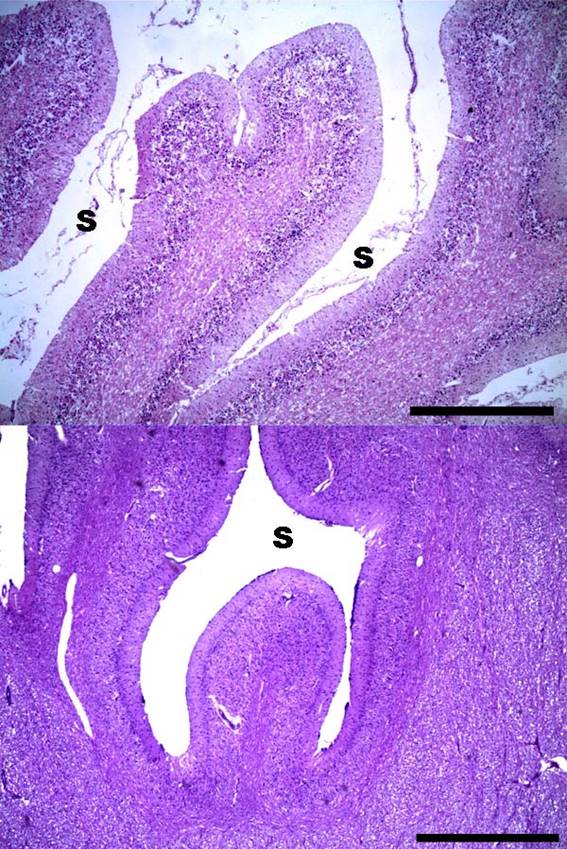

Se observó además adelgazamiento de las folias cerebelosas acompañado de expansión de los surcos tanto en el canino como en el equino (figura 3).

Figura 3: Abiotrofia cortical cerebelosa. Adelgazamiento de la folia cerebelosa y expansión de los surcos. Arriba: canino, abajo: equino. S = surco. HE. ×40 (escala equivale a 750 µm).